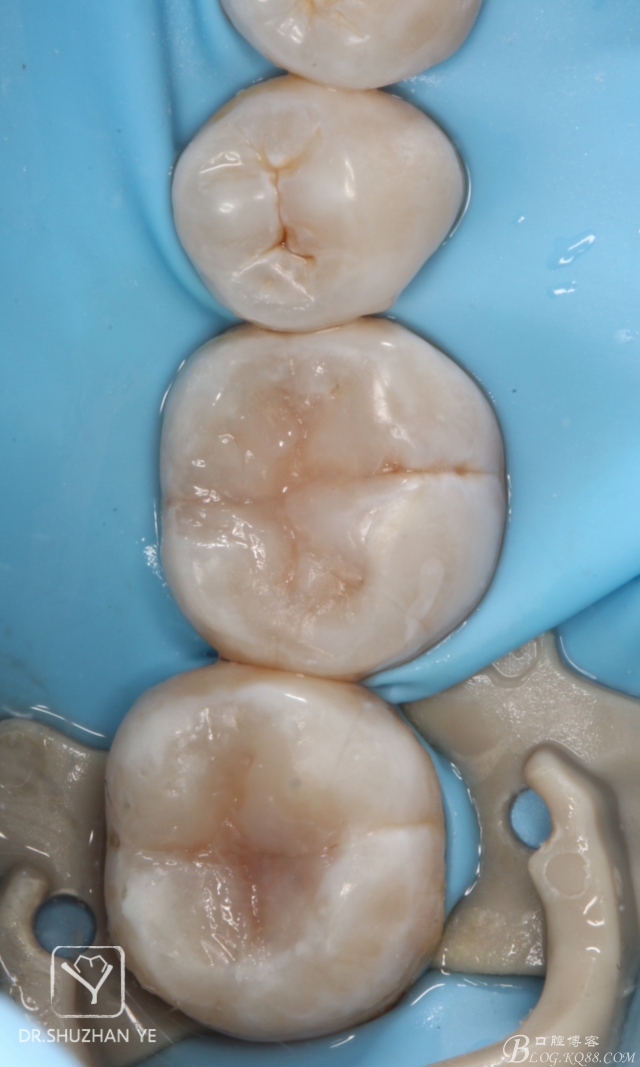

11、復(fù)診拋光完成

20151205082712_63035.jpg

總結(jié)體會(huì):印章法對(duì)于頜面窩溝點(diǎn)隙的齲壞,且頜面完整的病例比較適用,提高了窩溝塑性的效率和準(zhǔn)確性,能大大節(jié)約臨床操作時(shí)間,而并且因?yàn)槭侵苯釉螒B(tài)復(fù)制,所以完成后基本不需要調(diào)合,能節(jié)約不少時(shí)間,也在最大程度上保護(hù)了原有的咬合關(guān)系,同時(shí),在美觀上也能符合患者及醫(yī)生自己的要求。